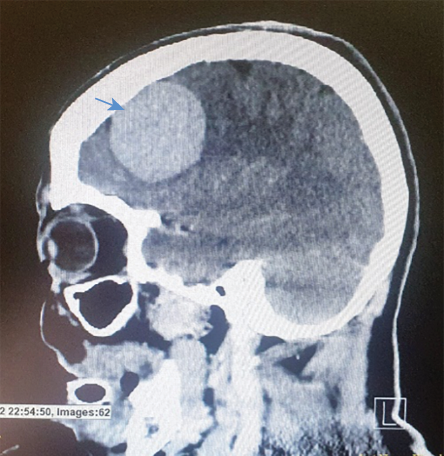

Six days after the cesarean section, the patient developed status epilepticus and was admitted to the intensive care unit with inotropic support, under the care of a multidisciplinary team comprising intensive care unit anesthetists, an obstetrician, a neurosurgeon, a general physician, and a gynecologic oncologist. Her electroencephalogram revealed focal epileptiform activity in the right fronto-temporo-parietal region for which she was put on antiepileptic medications. Computed tomography (CT) brain angiography [Figure 2] and MRI brain with gadolinium revealed a right frontal meningioma, but an immediate intervention was ruled out in view of her critical condition. She developed a fever, and a swab culture from the cesarean skin wound showed growth of Escherichia coli with extended-spectrum beta-lactamases. Her initial aerobic and anerobic blood cultures, high vaginal swab, and urine culture showed no growth. Sputum culture revealed scanty growth of multidrug-resistant organism Pseudomonas aeruginosa and Acinetobacter baumannii. Tests yielded negative for Brucellae, Coxiella burnetii, tuberculosis pathogen, TORCH pathogens, HIV, and other viral and fungal pathogens. CT of chest, abdomen, and pelvis revealed left lung consolidation/collapse without pleural effusion. Mild ascites was present. One week later, repeat CT revealed left lung consolidation/collapse in addition to left pleural effusion, with no obvious pulmonary embolism. The ascites was increasing. The ultrasound image of the chest revealed moderate left-sided pleural effusion with atelectatic left lower lobe. Echocardiography was normal.

Figure 2: CT scan of sagittal view of the brain showing the meningioma.